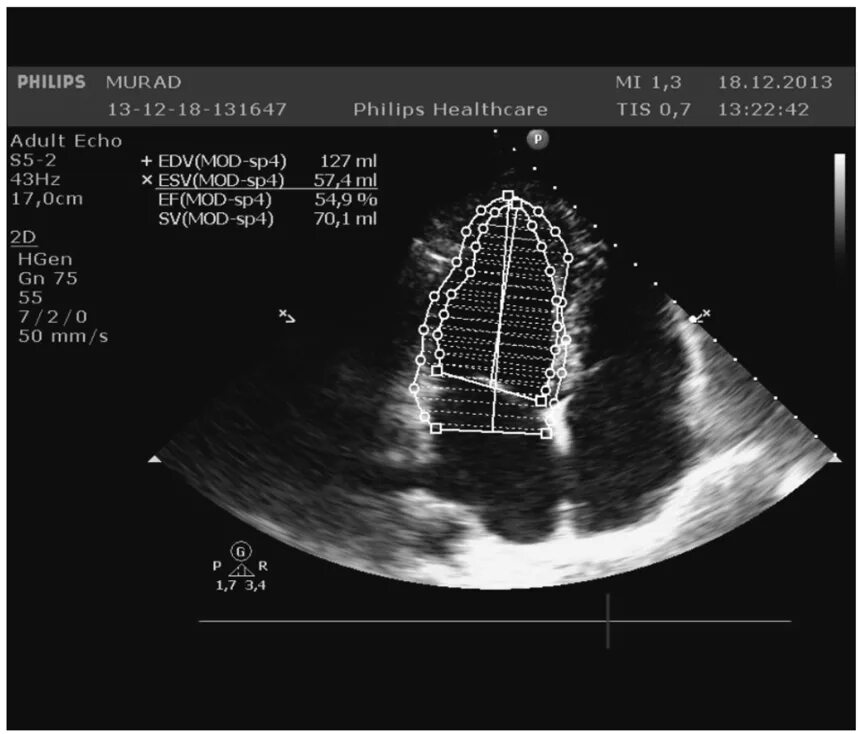

Размеры полостей сердца